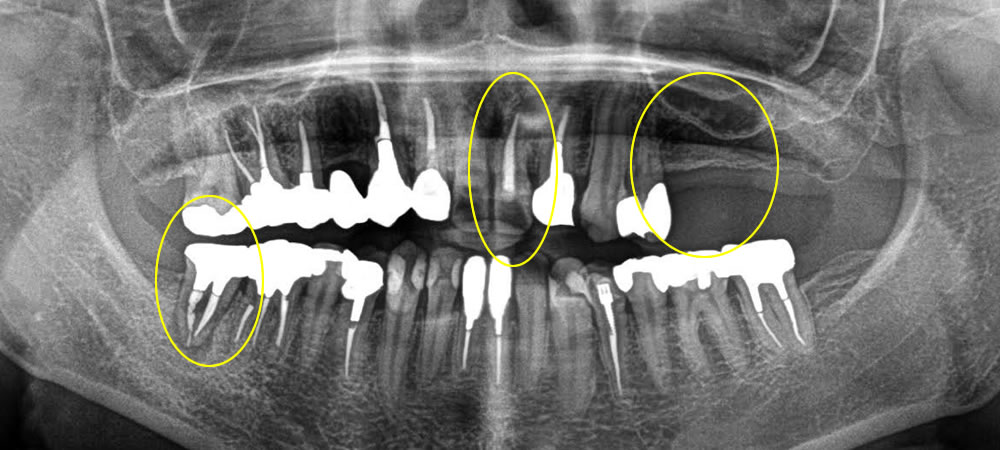

根尖性歯周炎の歯を抜歯即時埋入インプラントで治療した症例

年齢

50代

性別

男性

症例を見る